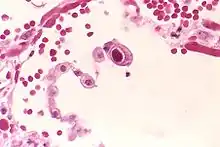

Typical "owl eye" intranuclear inclusion indicating CMV infection of a lung pneumocyte

Typical "owl eye" intranuclear inclusion indicating CMV infection of a lung pneumocyte[1]